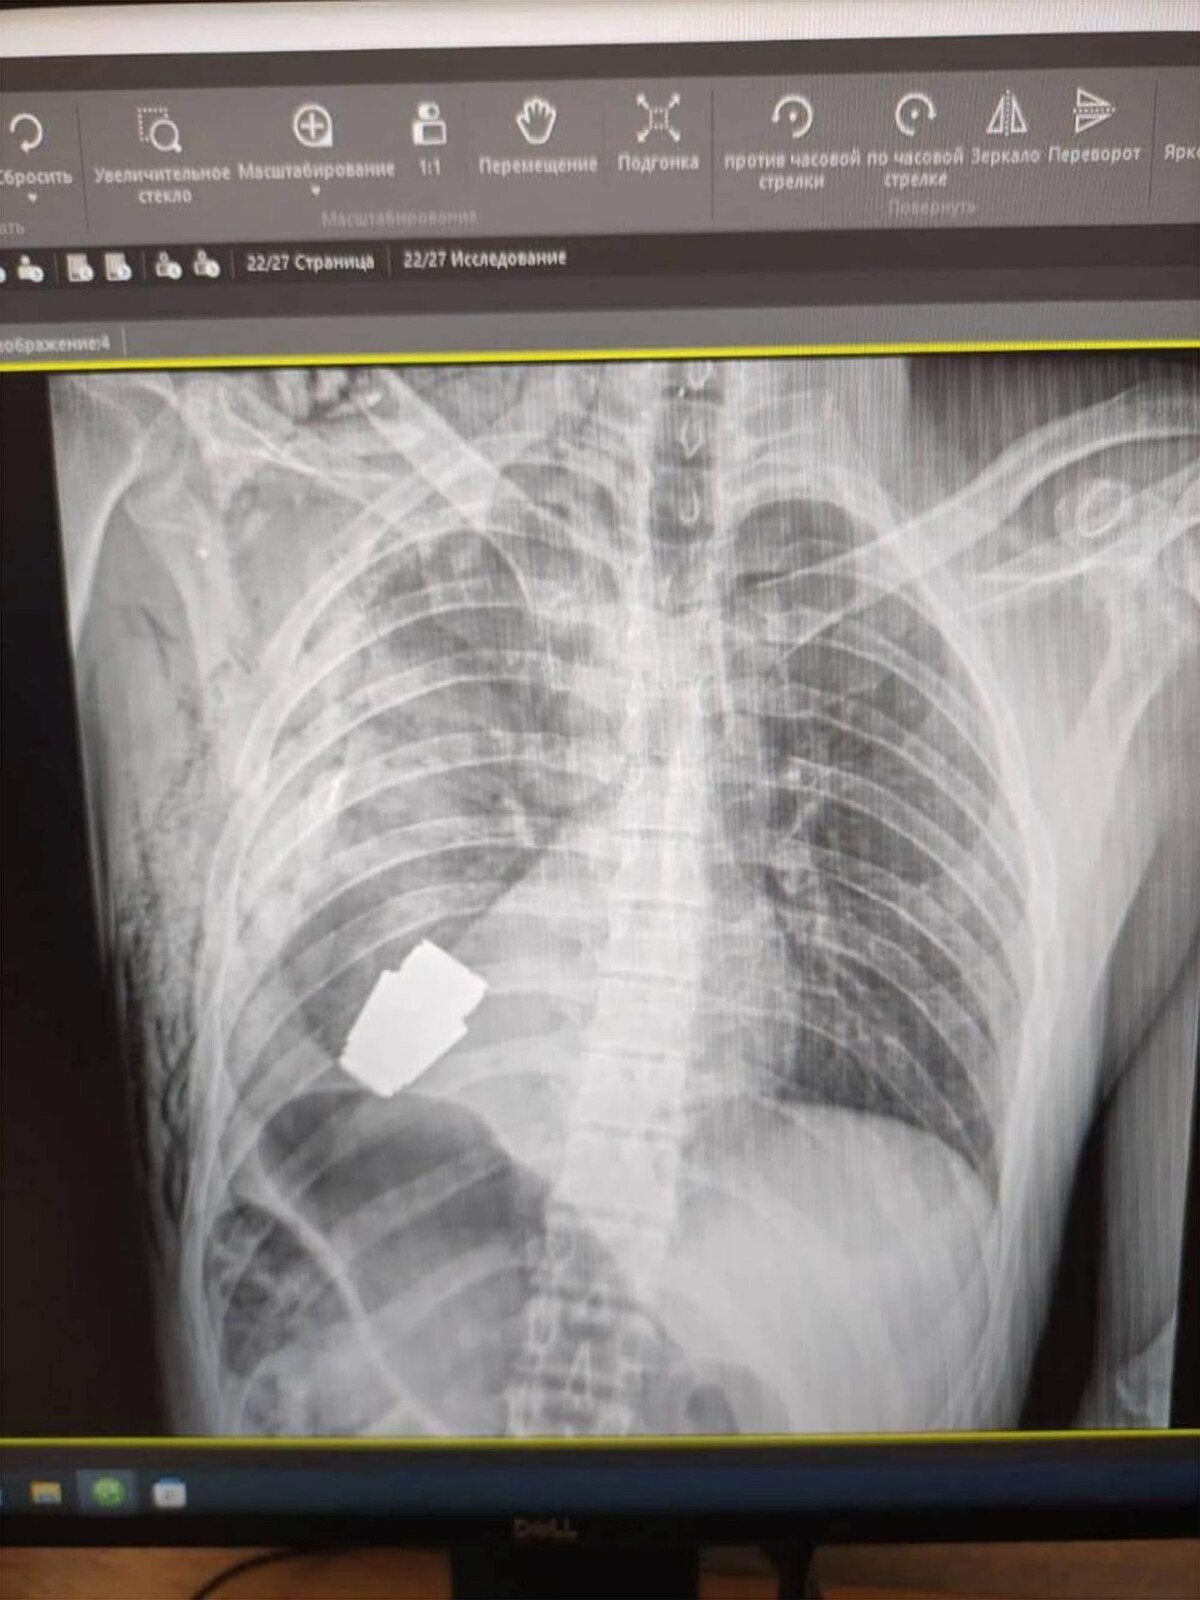

Na röntgenovej snímke, ktorú zverejnila ukrajinská armáda, je údajne aktívny granát, ktorý môžeme vidieť v hrudi vojaka.

Na röntgenovej snímke, ktorú zverejnila ukrajinská armáda, je údajne aktívny granát, ktorý môžeme vidieť v hrudi vojaka. Zdroj: General Staff of the Armed Force